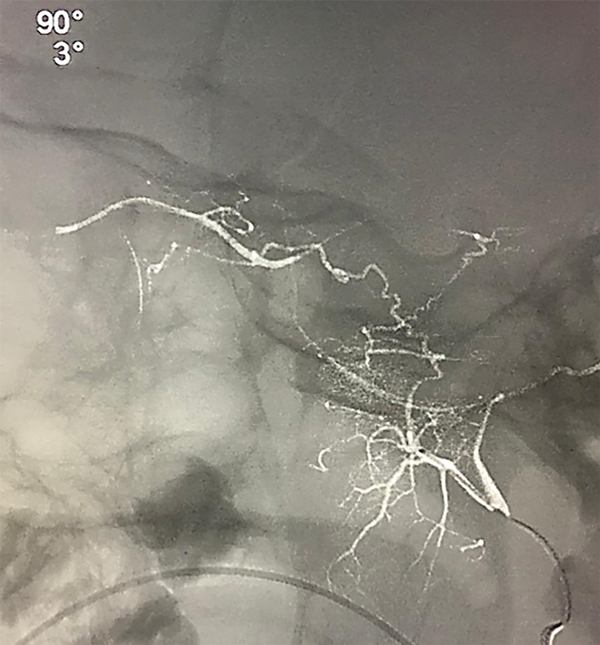

Puede presentarse la situación de observar escaso reflujo hacia la arteria carótida interna durante la adquisición superselectiva, esto no disminuye la efectividad siempre y cuando se logre una correcta opacificación de la coroides y se inyecten las drogas de manera pulsada y suave, según lo descripto por Jabbour et al. Si la maniobra no es satisfactoria se vuelve a repetir este paso. Si luego de dos (hasta tres) maniobras no se consigue cateterizar la arteria oftálmica se asume que no tiene un ostium “favorable” por lo que se da lugar a la siguiente fase de la técnica. Se posiciona el microcatéter en la arteria carótida externa y se cateteriza super-selectivamente la arteria meníngea media (o meníngea accesoria) para visualizar la anastomosis con arteria oftálmica (técnica 2 en 2 completa, fig. 5 y 6).

Fig 5: Cateterización superselectiva de arteria meníngea media (AMM) derecha, se observa anastomosis con arteria oftálmica homolateral y correcta opacificación de la coroides. Técnica “en dos pasos” o técnica “2 en 2 completa”. Vista lateral estricta. Microcatéter Magic 1.5.

Fig 6: Cateterización superselectiva de arteria meníngea media (AMM) izquierda bajo road-mapping. Técnica “en dos pasos” o técnica “2 en 2 completa”. Vista lateral estricta. Microcatéter Marathon 1.5.